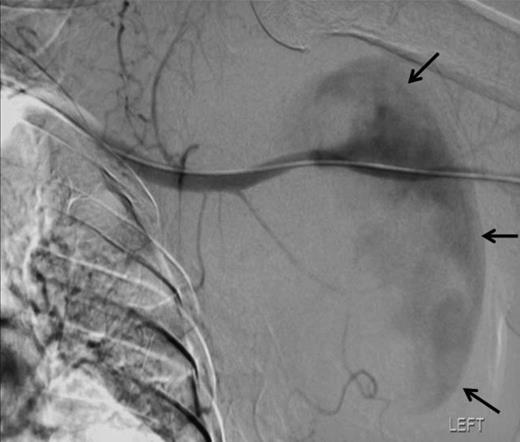

Angiographic localisation of the lesion in the third part of the axillary artery. Please note extravasation of contrast into the sac (arrows)

To attempt endovascular repair, an operative approach to the brachial artery preceded retrograde insertion of a 6cm long, 8mm thick Fluency nitinol self-expanding PTFE covered stent (Bard). This excluded the lesion successfully (figures 4 and 5). The haematoma was decompressed. Aspirin 75mg and clopidogrel 75mg were initiated for stent protection. The patient suffered a postoperative axillary wound infection which was treated successfully with antibiotics. There had been no recovery of neurological function in the arm. Neurophysiological studies revealed a proximal axonotmesis with a poor prognosis.